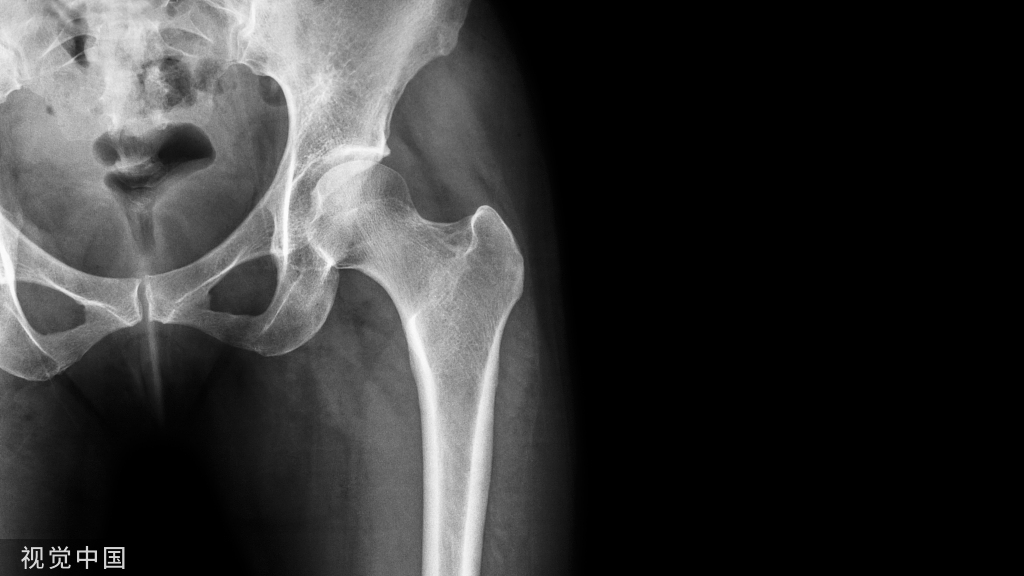

锻炼可以增加骨的合成代谢,可减少跌倒风险,并可有效降低老年人的整体骨折发生风险,特别是老年女性髋部骨折的发生风险。虽然锻炼对骨密度 提升作用有限,但仍建议患有骨质疏松症患者选择可负担且能够长期坚持的负重锻炼方式。